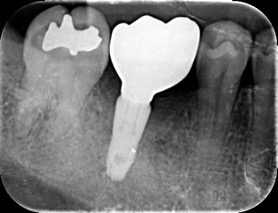

牙周補骨植牙-陳珮儀醫師

因嚴重牙周病所喪失的骨頭,可透過補骨再生方式重建,最後以微創方式人工植牙

治療前

治療後